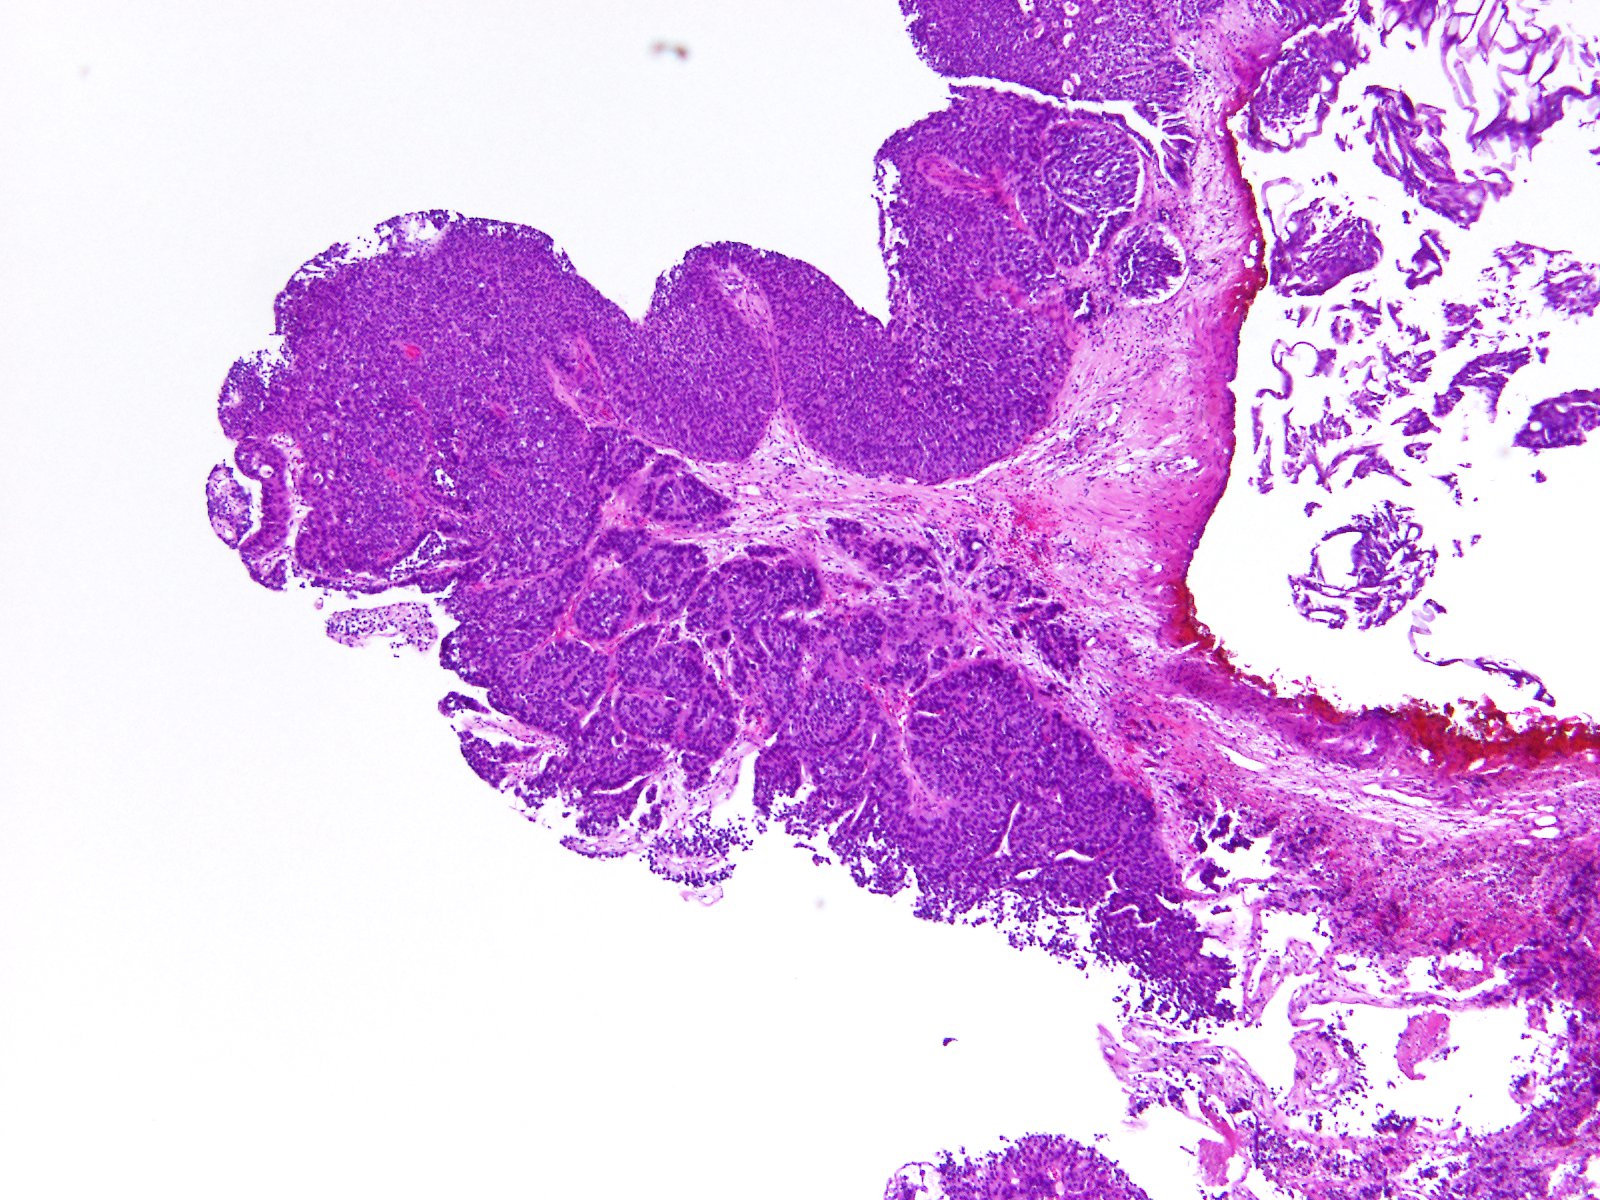

Bladder Papillary Lesions

Case ID: 357

13 Oct, 2015